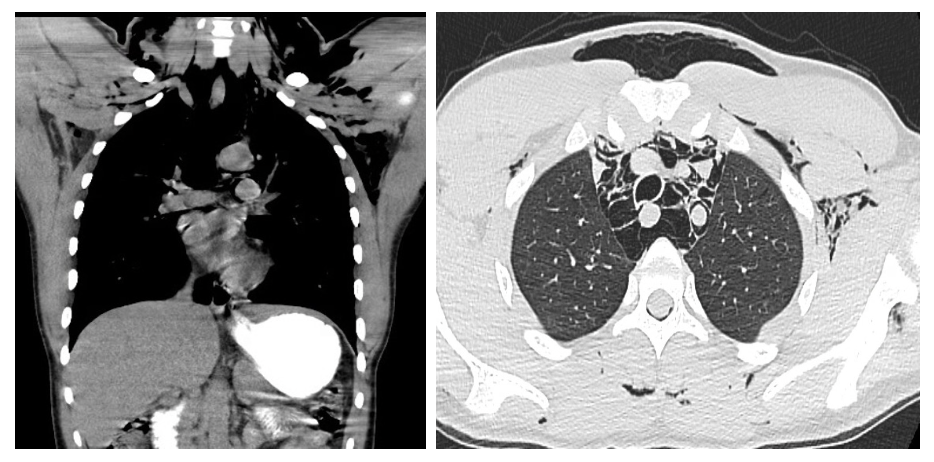

Figure 2,3: CT chest with oral contrast: Extensive pneumomediastinum and subcutaneous emphysema, without evidence of esophageal perforation  |

Initial chest radiograph demonstrated pneumomediastinum and subcutaneous emphysema in the neck and upper thorax. A CT chest with oral contrast was obtained to evaluate for esophageal perforation, given the presence of pneumomediastinum and subcutaneous emphysema in the setting of repeated emesis. Imaging confirmed extensive pneumomediastinum and subcutaneous emphysema, but no contrast extravasation, no pneumothorax, and no radiologic evidence of esophageal rupture were identified. These findings effectively ruled out esophageal perforation, supporting a diagnosis of spontaneous pneumomediastinum secondary to barotrauma from forceful vomiting. Laboratory evaluation was notable for leukocytosis (WBC 16.2 × 10⁹/L), acute kidney injury (creatinine 2.31 mg/dL, which improved with IV fluid resuscitation), and a positive urine drug screen for THC. Arterial blood gas (ABG) revealed a mixed alkalosis: primary respiratory alkalosis with secondary metabolic alkalosis (pH 7.62, pCO₂ 27 mmHg, HCO₃⁻ 28 mmol/L).